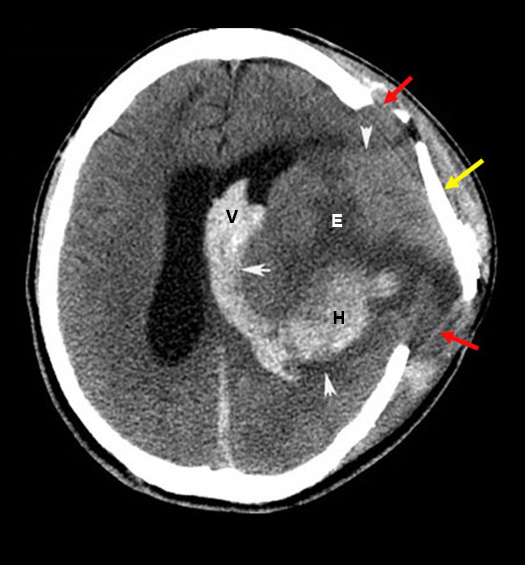

intracerebral Hemorrhage extending into ventricles

Case 8:

Post op non-contrast CT brain study done after recent craniotomy. Post op CT demonstrates hemorrhage within the deep frontal lobe that has ruptured into the left lateral ventricle.

Imaging findings:

Figure 8. Pre-contrast axial CT

- Left deep frontal lobe hemorrhage (H) that has ruptured into left lateral ventricle (V).

- Arrowheads point to edema (arrowheads). E is edema.

- Yellow arrow points to displaced craniotomy flap from brain herniation (red arrows).

- Small white arrow points to compressed left lateral ventricle.